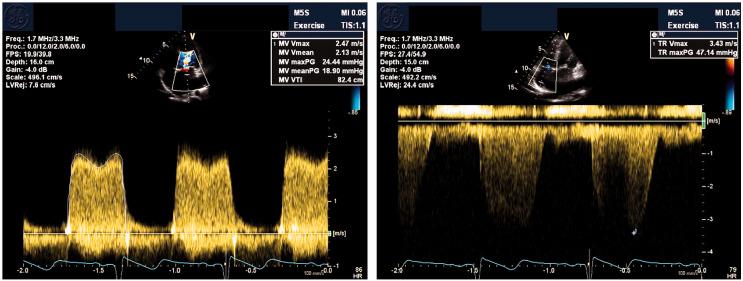

A 28-year-old aboriginal woman with known severe MS was found to be pregnant during routine health review, despite contraceptive efforts. Echocardiography demonstrated mean mitral valve (MV) gradient 14 mmHg; stress echocardiography demonstrated increased MV gradient 28-32 mmHg at peak exercise and post-exercise pulmonary artery pressure 56 + 3 mmHg with marked dynamic D-shaped septal flattening. Left ventricular systolic function remained preserved. She remained remarkably asymptomatic and underwent successful elective induction of labour at 34 weeks. Postpartum, she remained euvolaemic despite worsening MV gradients and new atrial fibrillation (AF). She subsequently underwent balloon mitral valvuloplasty with good result.

一名28岁患有严重MS的原住民女性在常规健康检查中被发现怀孕,尽管采取了避孕措施。超声心动图显示二尖瓣(MV)平均梯度为14 mmHg;负荷超声心动图显示运动峰值时MV梯度增加至28 - 32 mmHg,运动后肺动脉压为56 + 3 mmHg,伴有明显的动态D形室间隔扁平。左心室收缩功能保持正常。她一直没有明显症状,并在34周时成功进行了择期引产。产后,尽管MV梯度恶化且出现新的心房颤动(AF),但她仍保持血容量正常。随后她接受了球囊二尖瓣成形术,效果良好。